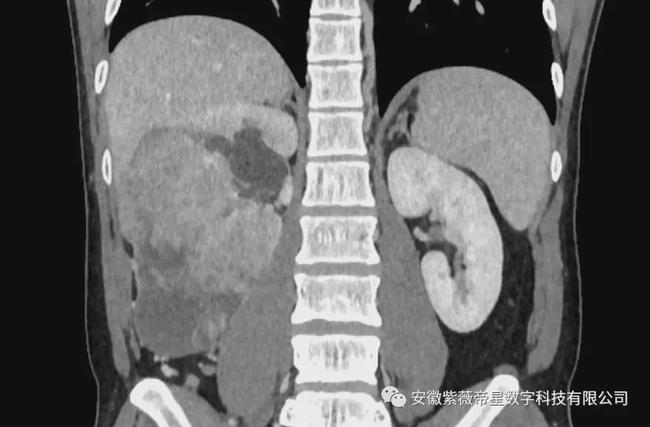

冠状面

临床病史: 患者男,35岁,右肾区疼痛三月余,入院检查CT显示,右肾中下极见巨大软组织密度团块影,长度约14.8cm,其内密度不均匀,增强扫描明显强化,与右侧肾盂、肾盏及输尿管移行部分界不清,贴近临近肝脏、下腔静脉。右侧肾盂、肾盏扩张、积水。右肾未见明显异常强化。